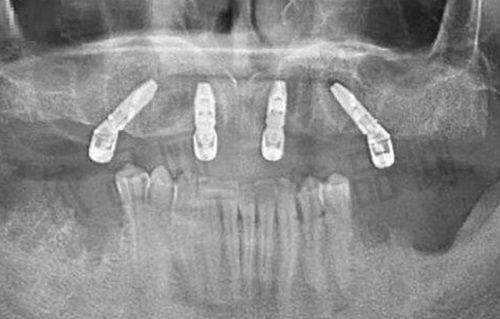

种植牙塑钢牙冠:种植牙是一种较为精良的牙齿缺失修复方式,而塑钢牙冠则是一种美观、耐用的牙冠材料。合肥天鹅湖口腔在种植牙塑钢牙冠方面有着丰富的经验,医生会根据患者的口腔情况和需求,选择合适的种植体和牙冠,为患者打造出自然美观、功能良好的牙齿。